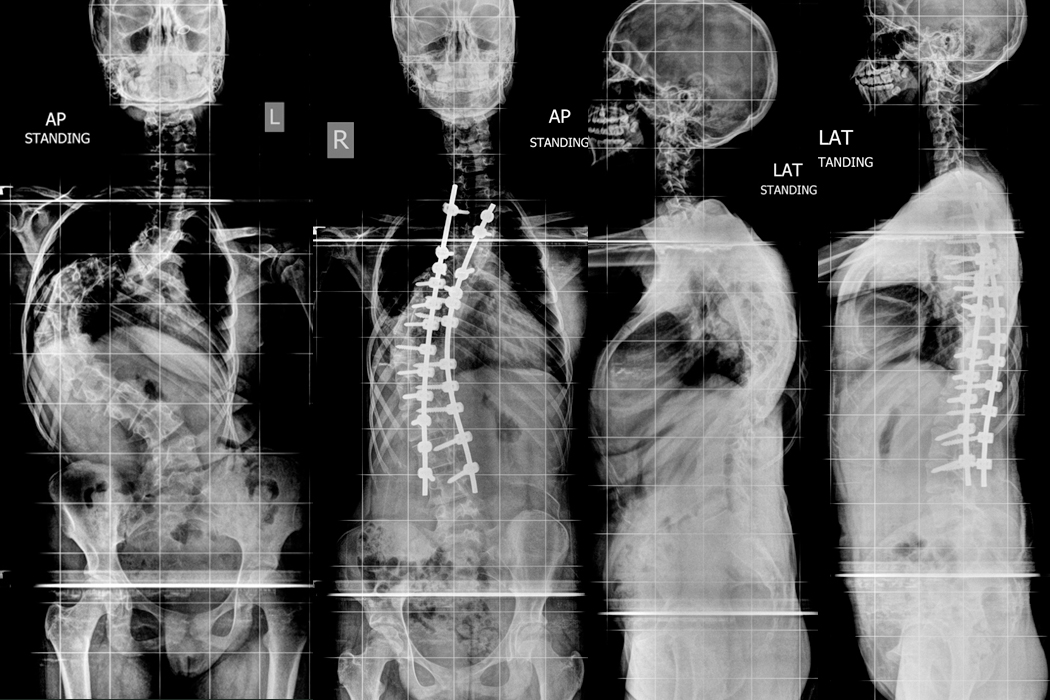

Patient C

11 year old kid presented with deformity of back with poor sitting balance and breathing problems. He was diagnosed with Spinal Muscular Atrophy with severe kyphoscoliosis when he was 4 years old. He was initially given Halo gravity traction to aid the surgery and improve his breathing function. Posterior Scoliosis correction done in stages on 25.08.2020 and 01.09.2020.

Hover over the image to view Pre & Post-op X-Rays